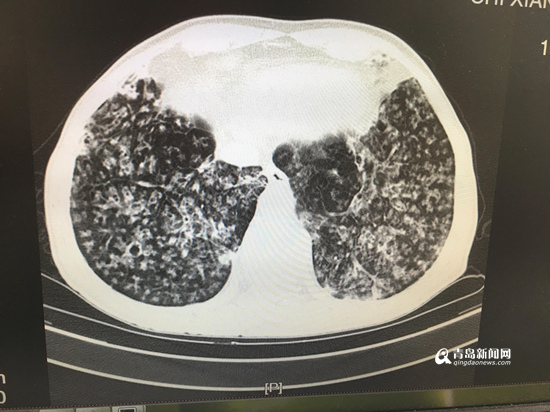

胸部CT显示病灶弥漫。

根据患者病情、影像学检查结果,经集团本部肺部感染诊疗中心主任兼西院区呼吸内科学科负责人、首席专家刘学东主任与西院区呼吸内科兰淑娟主任及专家团队共同研究、探讨,老人被确诊为“弥漫性泛细支气管炎”(简称“DPB”)。呼吸内科兰淑娟主任说:“DPB通常在40岁左右起病,初期有慢性咳嗽和脓痰,后期则表现为活动后呼吸困难且呈进行性加重。临床诊断标准包括必须项目项及参考项目。”必须项目三项,分别是:持续咳嗽、咳痰及劳力性呼吸困难;目前或过去有鼻窦炎;胸部X线示两肺弥漫性散在分布的颗粒样结节状阴影或胸部CT示两肺弥漫性小叶中心性颗粒样结节状阴影。参考项目三项,分别是:肺部可闻及啰音;FEV1/FVC<70%,PO2<80mmhg;冷凝集>=1:64。

兰淑娟主任表示:“该患者除症状符合描述,还曾因慢性鼻窦炎看过多年病。患者具有典型的影像学表现,符合DPB临床诊断标准。”